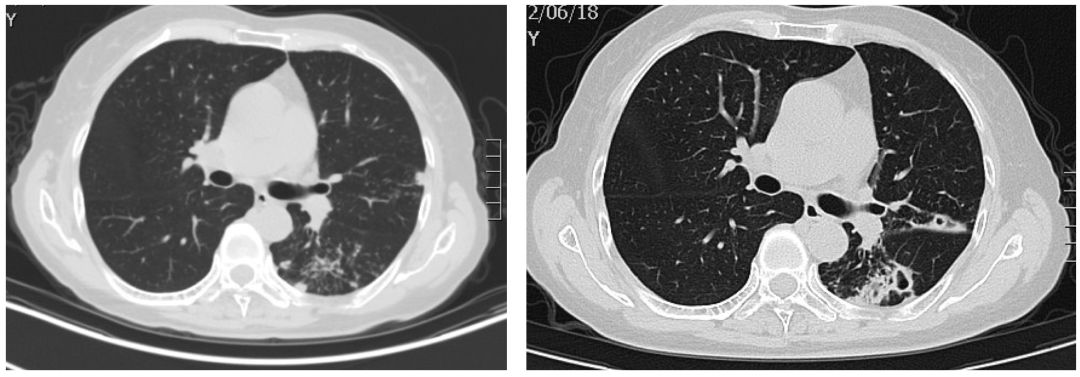

患者女性,66岁,反复咳嗽咳痰近3年。患者近3年来,多次查血沉基本正常,结核抗体阴性,结核杆菌T细胞检测(-),痰x-pert(-)。曾辗转多家医院就诊,均考虑肺结核,拟行抗结核治疗,患者拒绝接受肺结核诊断和抗痨治疗,症状时轻时重,症状重时就自行口服抗生素治疗。病因究竟是什么?是结核感染吗?该如何确诊?肺部CT如下:

左图:患病之初;右图:患病2年7月后

面对病人诉求,我们必须即刻开启病原学精准诊断之路。传统的痰检病原体检测是必须的,同时进行气管镜检查,观察肺内各支气管情况,肺泡灌洗获取下呼吸道标本,进行病原微生物二代基因测序。

非结核分枝杆菌(NTM)(海鱼分枝杆菌)